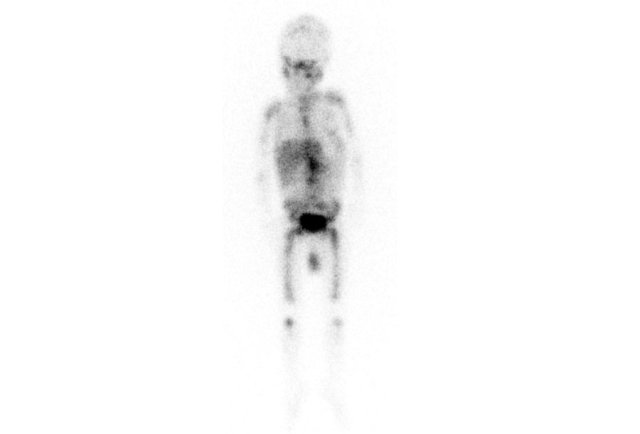

MIBG

All the activity indicates bone metastases.

In metastasized neuroblastoma follow-up imaging can be quite confusing, as bone metastases may become more apparent when they are successfully treated.